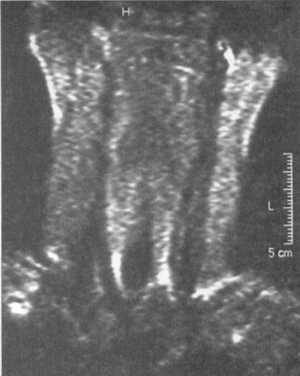

Ценную информацию о состоянии вывихнутых позвонков и спинного мозга дает

МРТ (рис. 2.6, 2.7). МРТ позволяет определить наличие зон ишемии в спинном

мозге (рис. 2.8, 2.9), состояние ликвородинамики (рис. 2.10).

Рис. 2.8. Компрессионный перелом с подвывихом кзади С4 позвонка

с зоной ишемии спинного мозга

Рис. 2.9. Вывих С4-С5, позвонков с зоной ишемии спинного мозга